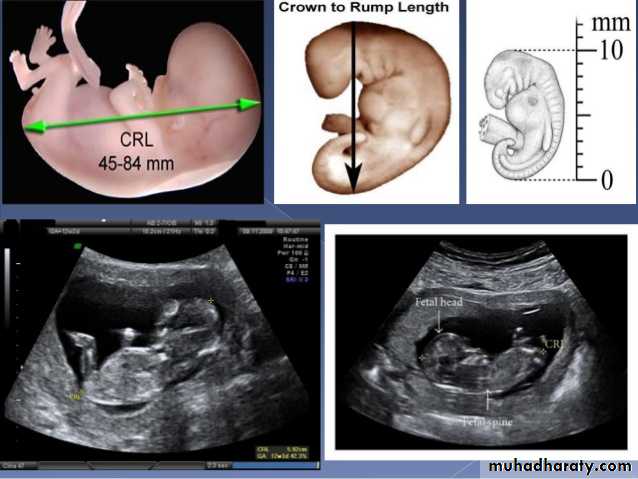

US of the obstetric & Gyne.BPD together with head circumference (HC), abdominal circumference (AC), and femur length (FL) are computed to produce an estimate of fetal weight. In the second trimester this may be extrapolated to an estimate of gestational age and an estimated due date (EDD) .